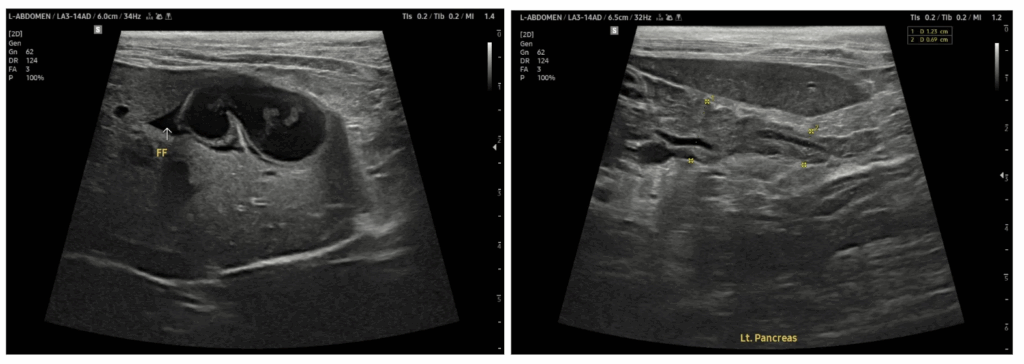

복부 초음파 검사에서는 기존 병력과 같이 췌장 비후가 지속적으로 관찰되었고, 담낭벽 비후가 함께 확인되어 담낭염 소견도 동반된 상태였습니다. 이러한 결과를 종합했을 때 췌장염과 담낭염이 함께 존재하는 상황에서 혈당 조절이 어려워지며 고양이 당뇨병성 케톤산증(DKA)이 발생한 것으로 판단하였습니다.

내원 첫날 복부 초음파 검사 결과

췌장 비후 및 담낭벽 비후 확인